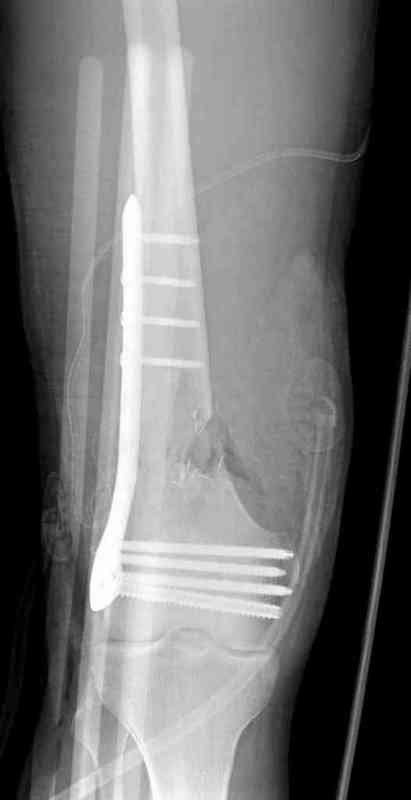

Пострадавшему 23, пистолетная огнестрельная не кроветочащая рана, меньше одного см диаметром, входное отверстие расположено латерально, и выход передне-медиально, и еще имеется второе пулевое ранение правой navicular bone с этой стороны.

Несмотря на сниженный до 0.9 BI-ankle-brachial-index (обязательное, недорогое исследование при подозрении на повреждение сосудов, рассчитанный по разнице давления в нижней и верхней конечности), последующее КТ ангиограмма не подтвердила повреждения артериальных сосудов.

Доступ был латеральный, при вскрытии с задней

поверхности бедра обнаружили кровотечение. Поднятием давления на заранее установленном турникете на конечности проконтролировали кровотечение.

В данном случае мы не ставили осуществление гемостаза приоритетным, после 30 минут больной оставлен вызванному сосудистому хирургу со стабильной фиксацией бедра. Несмотря на выбранный передне-медиальный доступ, хирург произвел восстановление сосудистого повреждения.

При близости сосудов к многооскольчатому повреждению костей, сперва необходимо удостовериться в наличии повреждения сосудов без применения турникета.

Сосудистые повреждения часто приводят к увеличению

давления в компартментах, мониторинг на голени показал увеличение, и поэтому сделана профилактическая латеральная фасциотомия.

Латерально пластину защитили ушиванием

илио-тибиального тракта, а медиальная сторона была ушита мышцей, и все раны закрыли ваккумированием (VAC)

На третий день после Irrigation & Debridment закрыли все раны за исключением компартментальной раны из-за отека, медиально в дефект кости установили Putty Grafton Bone Substitute. На компартментальную рану вакуум и мероприятия по сближению краев раны резиновой стяжкой.

На 9й день с момента травмы ушили рану без натяжения. Больной получает реабилитацию, движения коленного сустава с помощи CPM-continuous passive motion machine. Сегодня выписан.